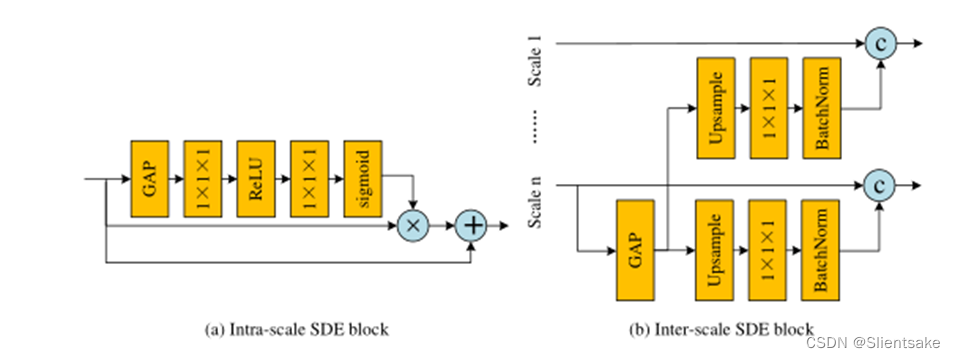

图4所示。(a)尺度内语义辨别增强块,(b)尺度间语义辨别增强块,©多尺度注意模块的结构。GAP, c〇,+〇,×〇分别表示全局平均池化,串联,元素式求和,矩阵点乘法。

在提议的HNF-Netv2中,作者在级联的PMF模块中部署了尺度间和尺度内的SDE块。如图3所示,作者在PMF模块的每个卷积分支内部构造尺度内的SDE块。同时,为了控制计算复杂度,作者只在第3个PMF模块和第4个PMF模块之间插入一个尺度间的SDE块。现在作者将深入研究这些关键组件的细节。

尺度间SDE模块采用PMF模块全连接融合块部署,结构如图4 (a)所示。作者首先对规模n(当前PMF模块中规模最小的分支)的特征应用一个全局平均池(GAP)层,获得具有高度语义信息的全局上下文。然后,作者将得到的特征分别上采样到PMF模块各分支的分辨率。考虑到上采样特征的空间信息较差,作者使用1×1×1卷积层将信道数减少到1,然后将其与高分辨率特征连接。在此设置下,作者可以在减少对原始空间信息破坏的同时,在高分辨率特征中增加全局语义识别。不同于inter-scale端模块,intra-scale端块每个回旋的分支及模块的内部构造与图4中所示的结构(b)。作者还利用一个缺口层生成全局上下文的特性和应用两个1×1×1卷积层调整频道号码。与基于cnn的分类网络的预测层相似,获得的全局特征从各个空间位置收集信息,具有较强的语义信息。因此,作者可以利用这些全局特征对输入的高分辨率特征进行重新加权,从而进一步增强全局语义识别能力。在之前的工作[10,9]之后,作者最终将多尺度增强特征串联起来作为EMA模块的输入。